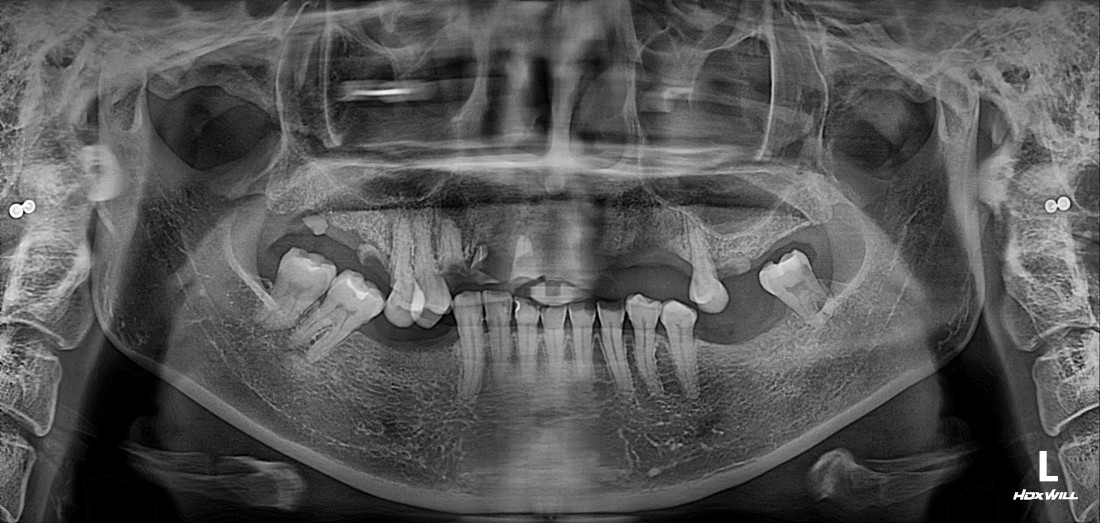

우리가 치아를 나눌 때에

윗니 (상악) / 아랫니 (하악) 이렇게

간단하게 구분을 하는데요.

일반적으로 상악임플란트는

하악에 비해 잇몸뼈가 얇은 경우가 많고

예뻐야 하는 심미적인 부분도

담당하기 때문에

특별히 신경써서 상악임플란트 수술경험이

풍부한 구강외과 전문의에게

진료받는 것을 추천드립니다.

광주 상악임플란트를 해야하는 때가 오면

무엇보다도 '예쁘고 잘 씹어지게'

임플란트 진료를 받고싶으실텐데요.